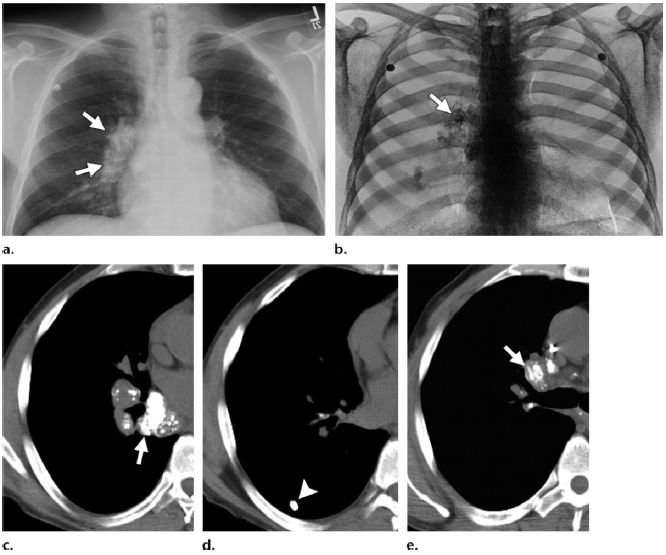

图1 胸片(a)和钙影像(b):男,53岁,不明原因的系统性淀粉样变性。影像学显示右肺门淋巴结钙化(箭头),(c~e)同一病人CT图像显示含有纵隔淋巴结钙化(箭头),和右肺下叶完全钙化的淋巴结(图d箭头)结节取活检证实为淀粉沉积。